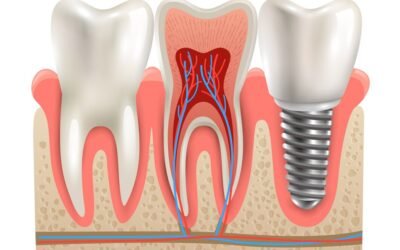

L’Importance des Implants Dentaires : Avantages, Types et Techniques

Les implants dentaires sont conçus pour imiter la structure d’une dent naturelle, ce qui les rend esthétiquement attrayants et fonctionnellement efficaces.